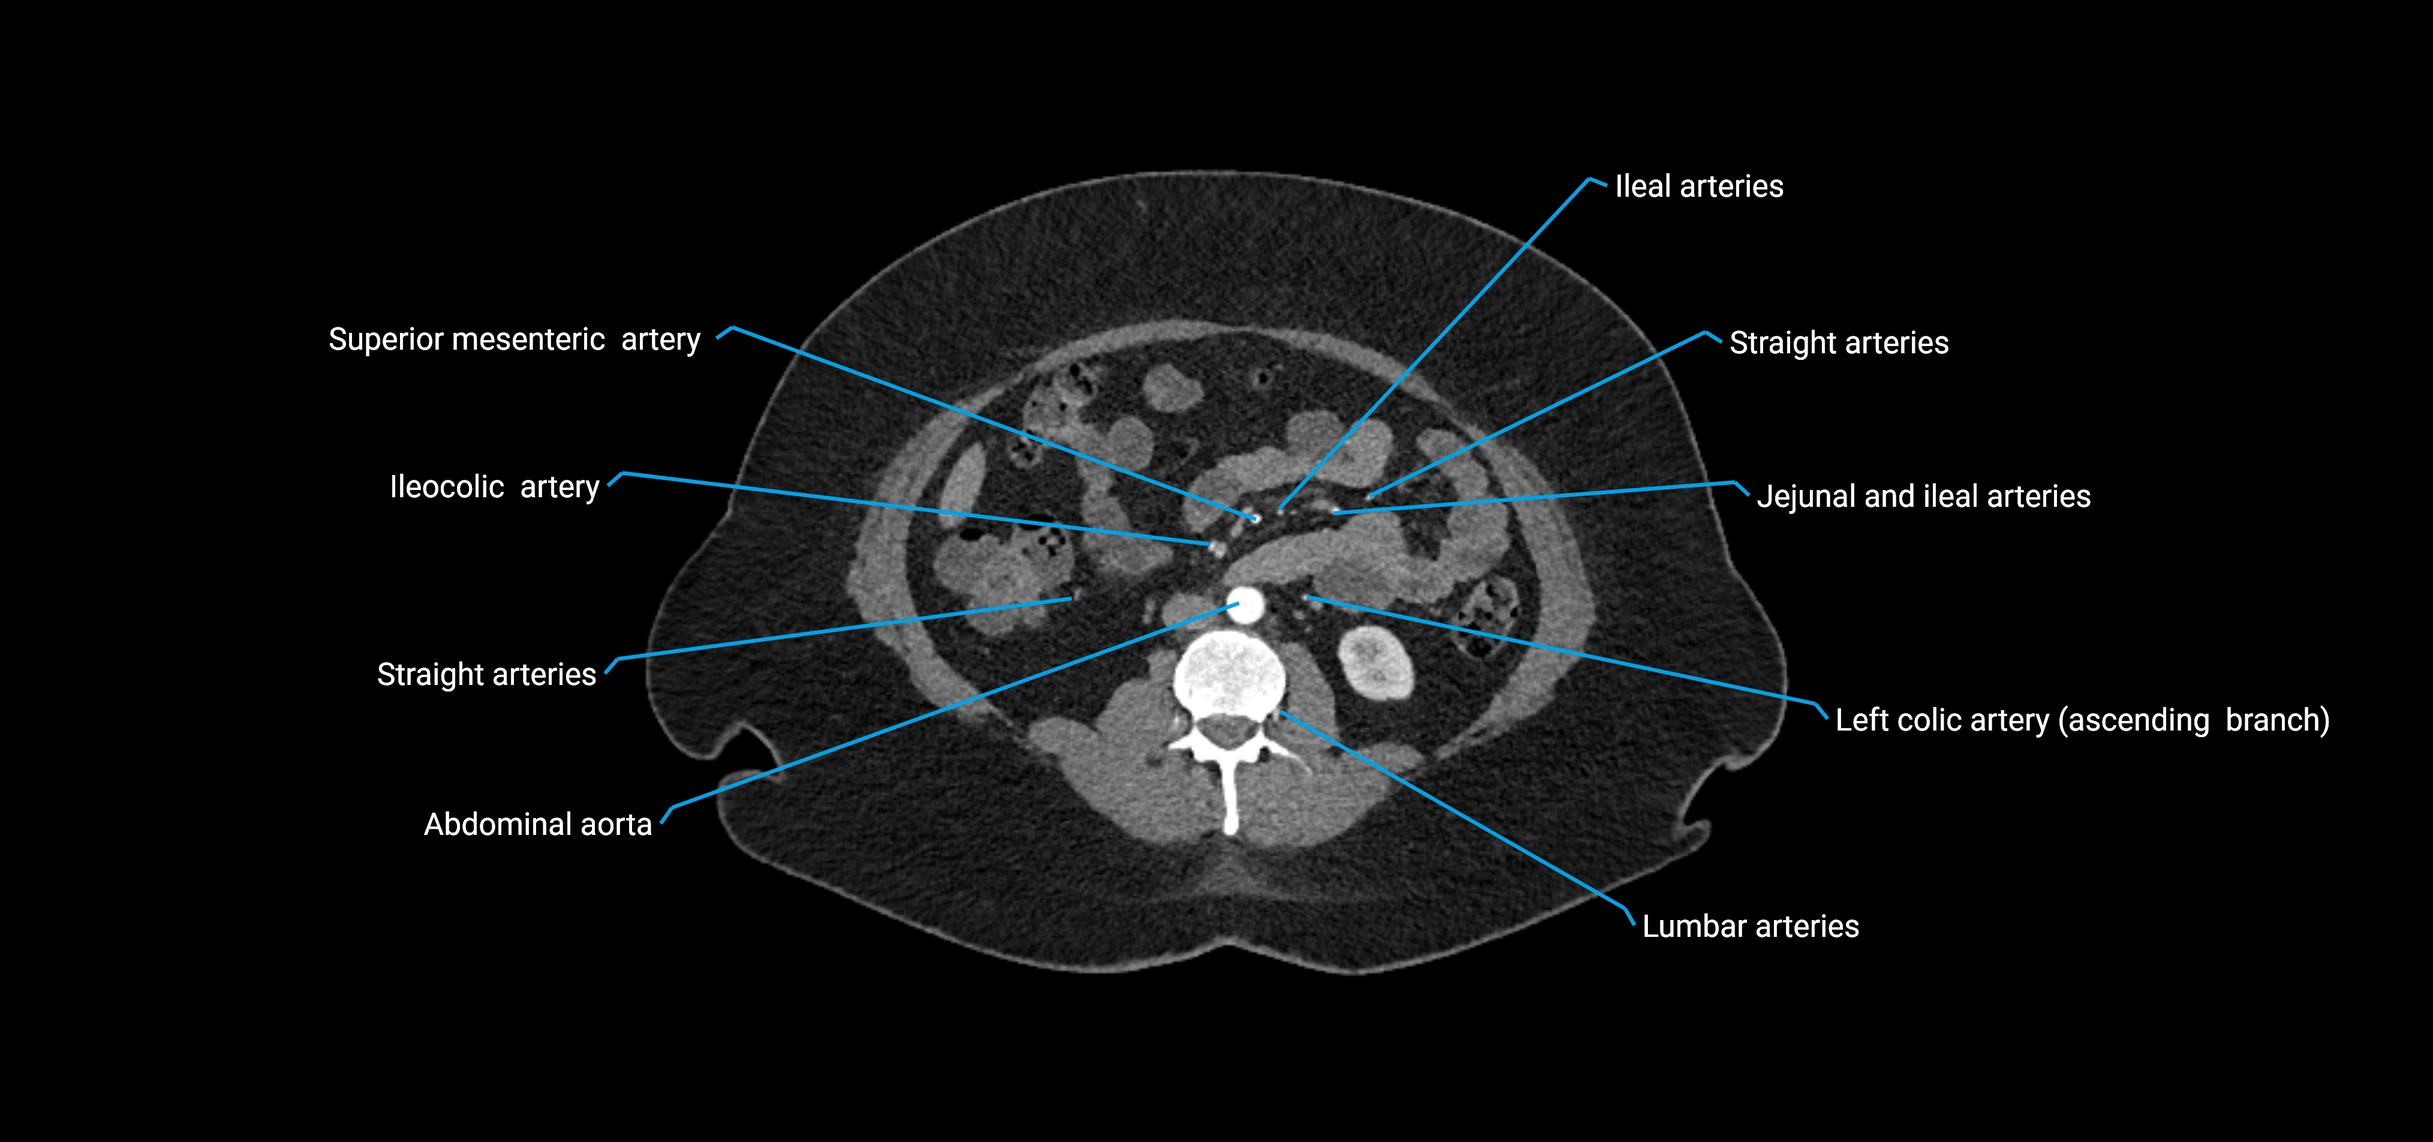

Contrast-enhanced CT (CTA):

• Gold standard for abdominal aortic imaging

• Provides excellent detail of lumen, wall, aneurysm, thrombus, and branch vessels

• Multiplanar and 3D reconstructions help in aneurysm measurement, stent graft planning, and dissection evaluation

• Detects acute rupture, traumatic injury, or occlusion with high sensitivity